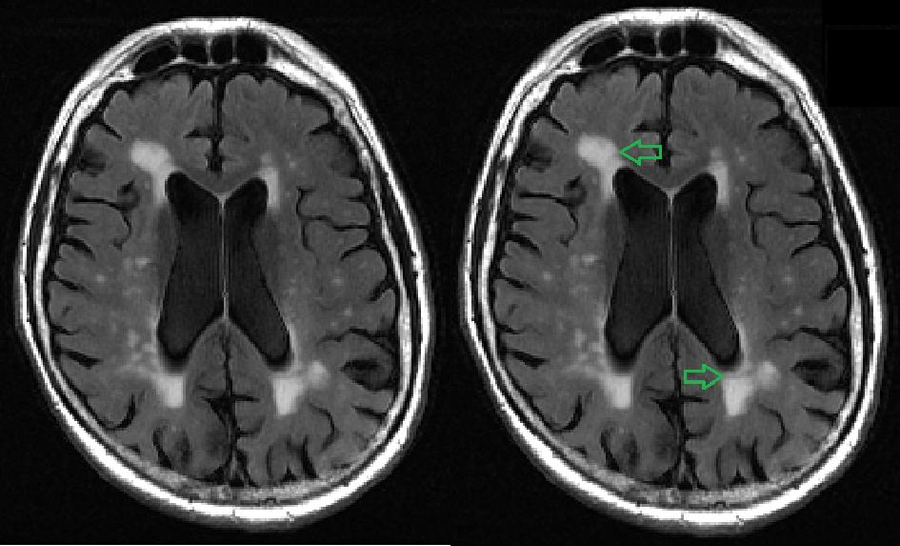

MRI examples of autoimmune dementia. (a) Bilateral T2hyperintensities Can Mri Pick Up Dementia But they’re not enough to diagnose dementia on their own. “can mri show if i have dementia?” in fact, we scan patients every day with a diagnosis of dementia, memory loss, alzheimer’s, and confusion, among a variety of other. An mri uses a powerful magnetic field and radio frequency pulses to create a detailed picture of the brain to detect. Can Mri Pick Up Dementia.